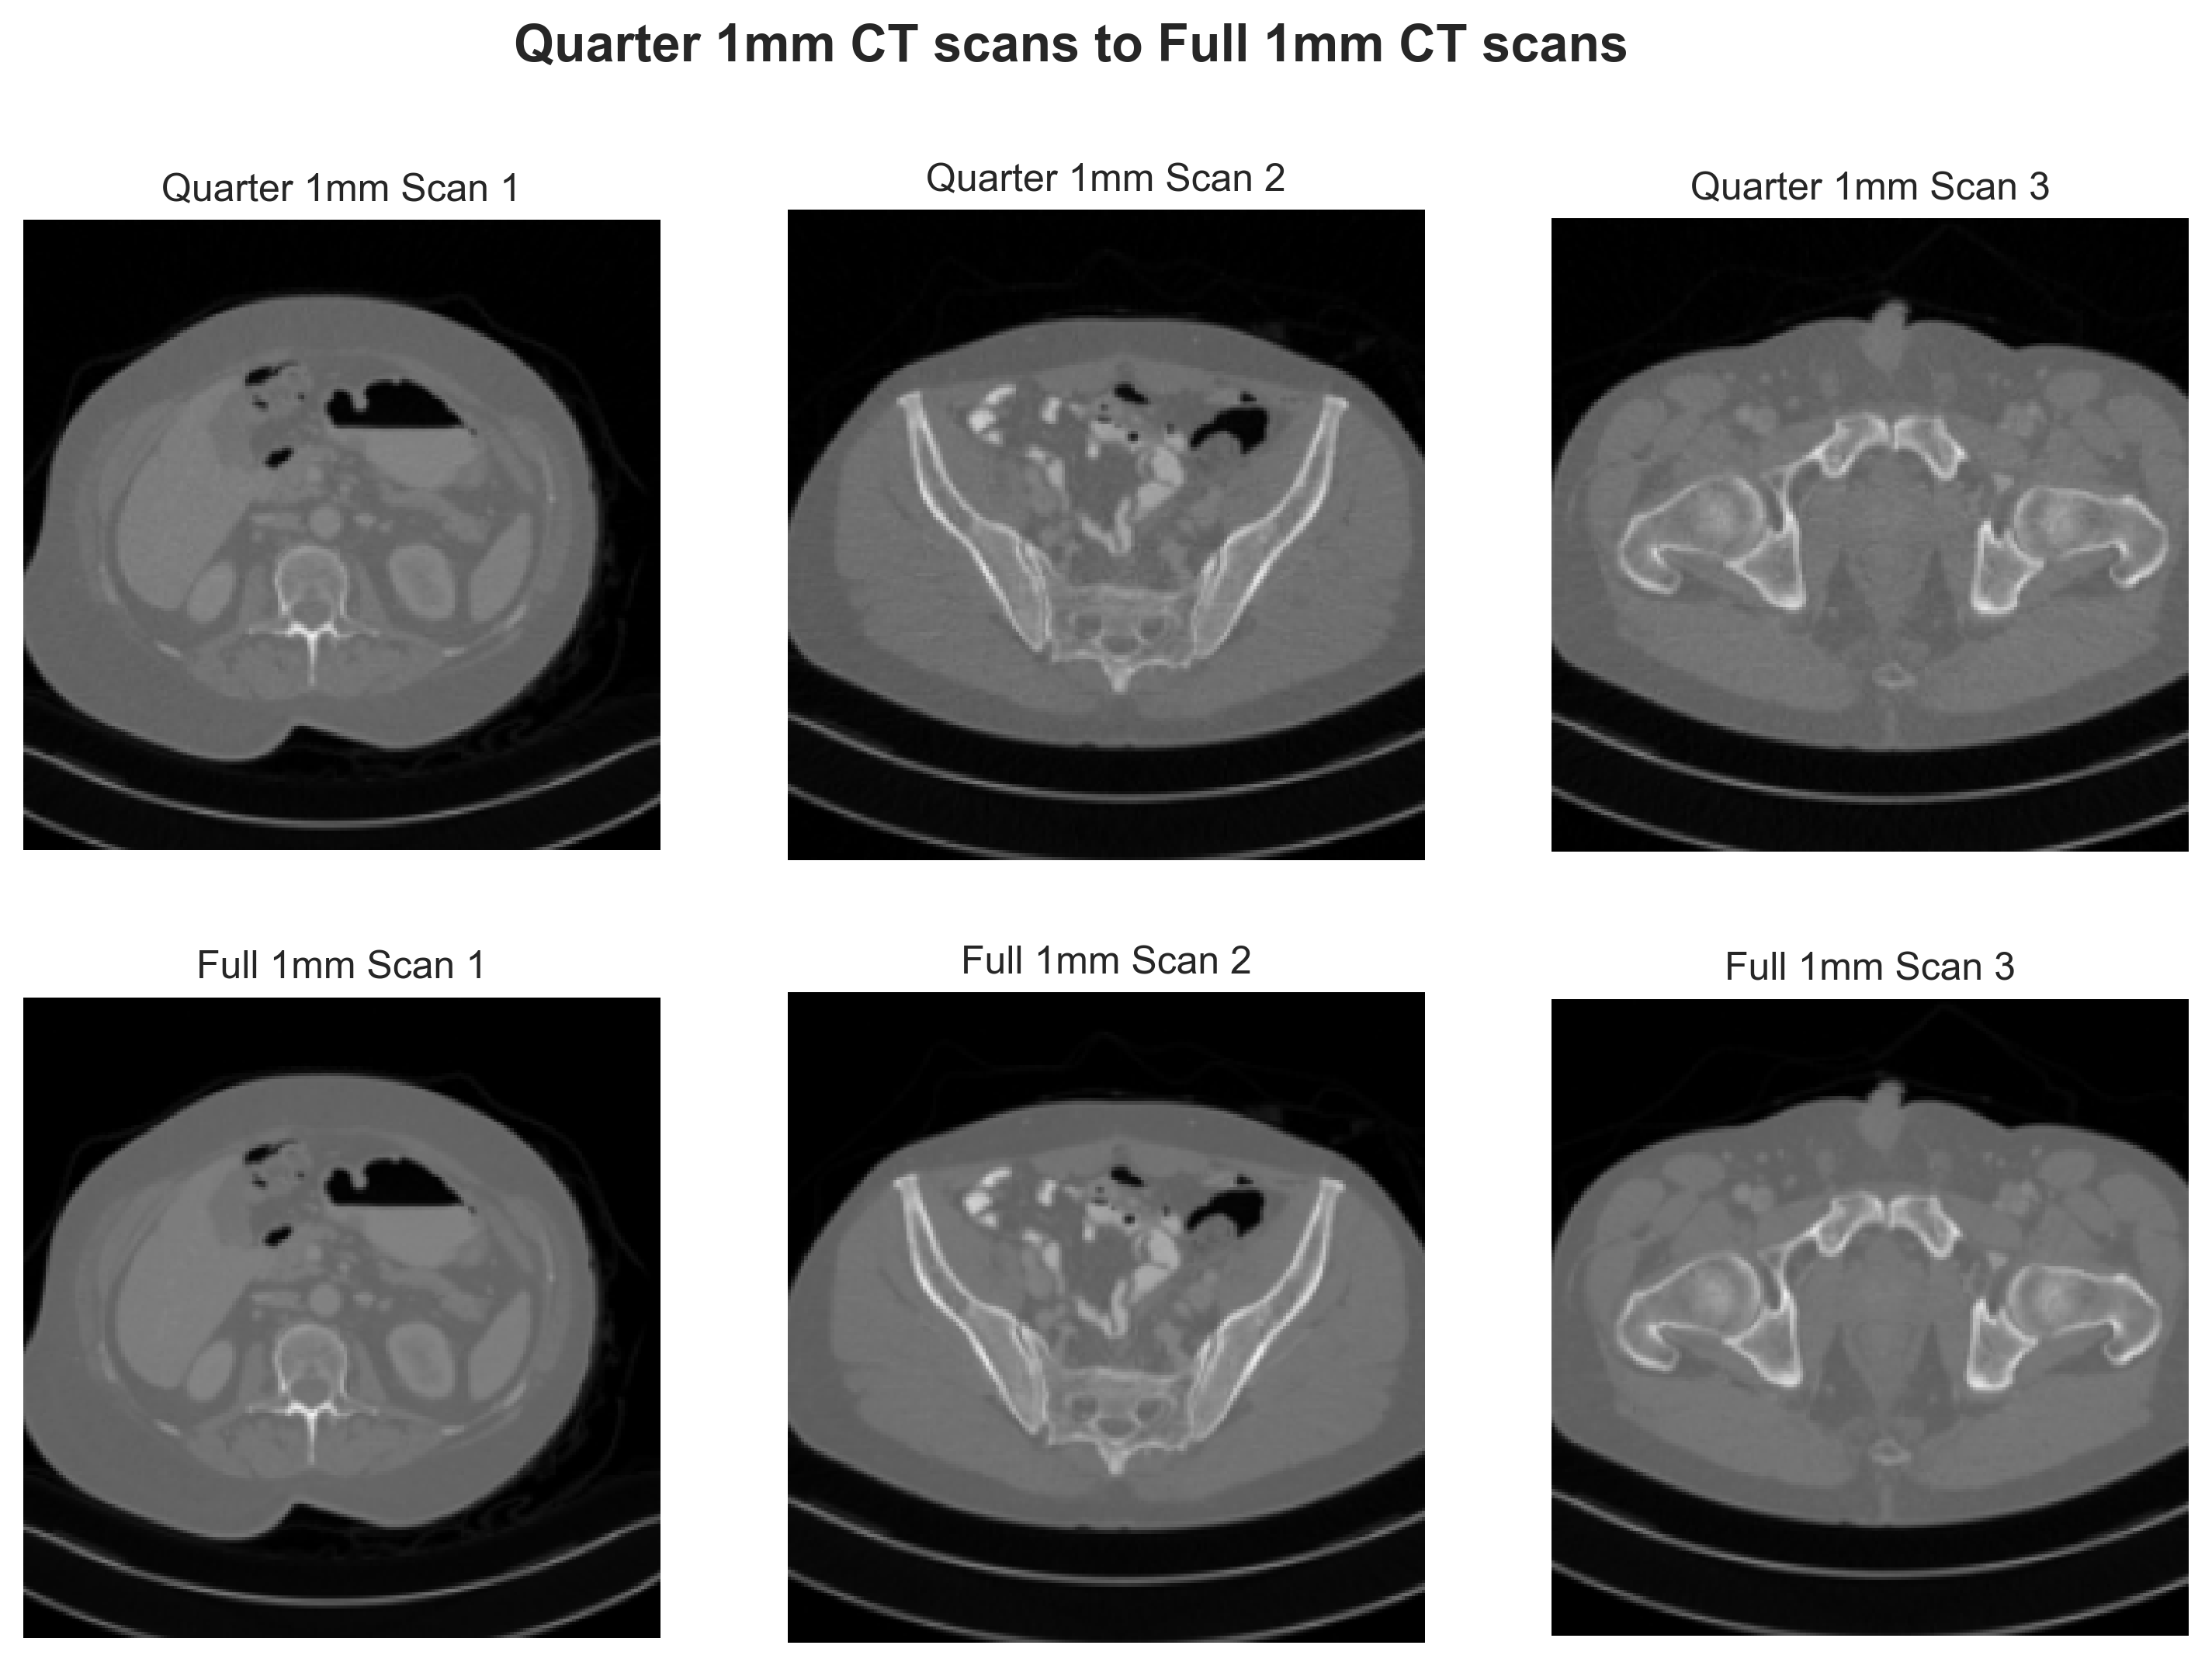

Our experiment utilizes the 2016 Low-Dose X-ray CT Grand Challenge dataset from the American Association of Physicists in Medicine (Mayo-2016) [23]. Mayo-2016 dataset comprises LDCT and NDCT images from 10 anonymous patient scans. We specifically use high-resolution 1 mm slice thickness ’quarter-dose’ subsets and the corresponding ’full-dose’ subset images. Look up Appendix A for visualized examples.

[Uncaptioned image]

Figure 7: Examples of quarter 1 mm and full 1 mm scans of Mayo-2016 Dataset.